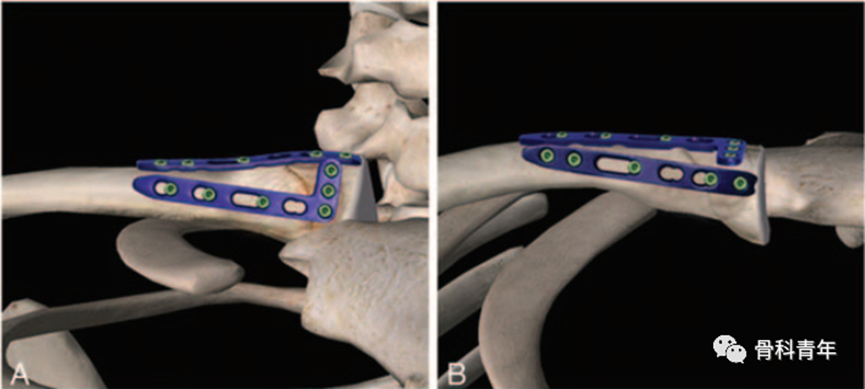

由于锁骨内侧软组织较薄弱,采用3.5/2.7mm钢板螺钉系统内植物容积较高,容易出现局部激惹甚至需取出内固定。为此,国外学者利用桡骨远端背侧钢板,塑形为双平面呈“90°”的新型内固定,内植物激惹小,疗效良好:

步骤二:桡骨远端背侧钢板(2.5mm,瑞士Aptus),塑形后呈“H”形,双臂呈90°。